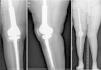

Descripción de la técnica quirúrgica a estudioLos componentes infectados se retiran de manera estándar (fig. 1A y 1B). Posteriormente se realiza un desbridamiento exhaustivo, incluyendo el canal endomedular en caso de prótesis con vástago. Antes de la administración de los antibióticos intraoperatorios, se toman al menos 6 muestras para el cultivo microbiológico. Después se realiza una irrigación a baja presión en todo el campo quirúrgico expuesto. Se evalúa el defecto óseo final tras el desbridamiento (fig. 2). En los casos que nos encontramos una pérdida extensa de fémur distal utilizamos un espaciador de cadera prefabricado (Vancogenx®, Tecres, Somatocammpagna, Italia) para construir una articulación tipo ball-and-socket. El espaciador de cadera se produce de manera industrial en fábrica, con un aspecto similar al de una hemiartroplastia de cadera fabricada con cemento acrílico impregnado con gentamicina y vancomicina. La parte interna del espaciador consiste en una varilla de acero inoxidable que proporciona estabilidad mecánica. Estos espaciadores están disponibles en 6 versiones: 3 tamaños de la cabeza (46, 54 y 60mm) con un vástago largo (275-290mm) o un vástago corto (153-168mm). Los espaciadores se impregnan con una concentración 1:1 de antibiótico, por lo que dependiendo del tamaño de la cabeza y la longitud del vástago, contendrán entre 1,1 a 3,2 g de ambos antibióticos (tabla 1). Según el defecto residual, se selecciona el tamaño del espaciador prefabricado. En la mayoría de los casos se utilizó el espaciador de cabeza pequeña (46mm). El espaciador de cadera se utiliza de manera «invertida», con la cabeza frente a la superficie de la meseta tibial remanente. La cabeza del espaciador se convierte en el componente «bola» de esta articulación ball-and-socket. Para construir el recipiente sobre la superficie de la tibia proximal, se utiliza cemento cargado con antibiótico. La mezcla se realiza sin vacío13 utilizando altas dosis de dos antibióticos termoestables sinérgicos, seleccionados según el perfil de sensibilidad antibiótica del microorganismo14. En la mayoría de los casos añadimos, por cada bolsa de cemento óseo de 40 gramos, 4 g de vancomicina en polvo y 4 g de tobramicina en polvo. En casos de infección protésica de una prótesis con vástago, el canal endomedular tibial se rellena con una barra de cemento con antibiótico hecha durante la cirugía; esto nos dará más estabilidad al espaciador y permitirá rellenar el espacio muerto del canal medular tibial.